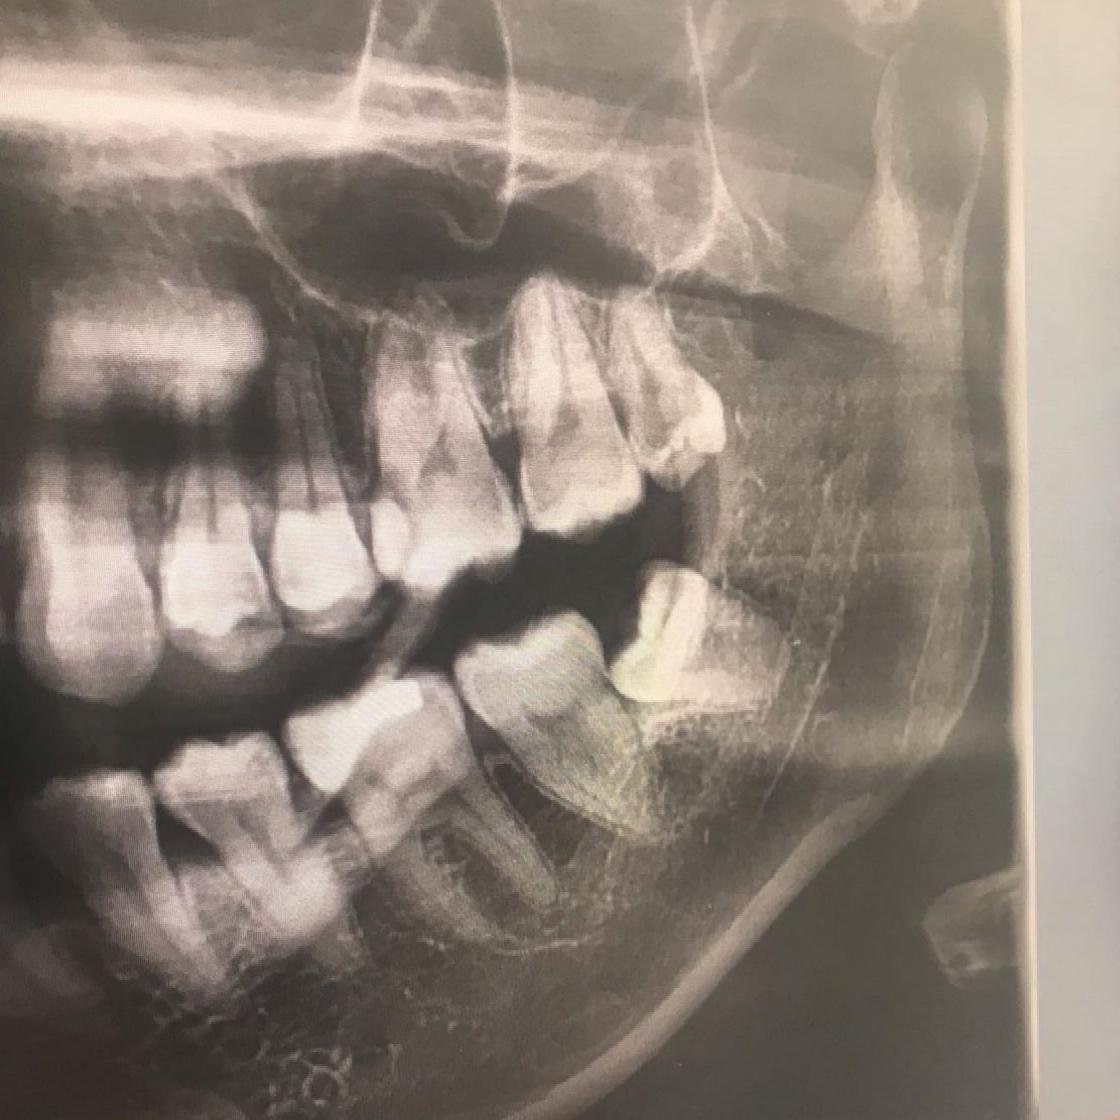

智慧齒(英文︰wisdom teeth)手術後面部都會腫脹3至5日,而手術後最擔心便是因處理不當,而導致面部持續腫脹或傷口再度發炎。以下就盤點5個智慧齒手術後的注意事項及術後必備的護理好物,讓大家可以在手術後多加留意,幫助舒緩因手術而引起的腫痛不適。

進行智慧齒手術後面部會明顯腫脹。 一般智慧齒都會深藏在齒槽骨中,令流血的情況較其他拔牙手術高。 由於傷口較深,一般都需要咬住棉花超過30分鐘內止血。